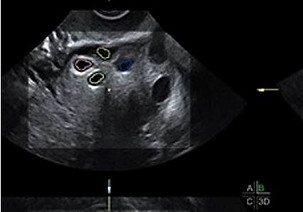

PROCREAZIONE ASSISTITA